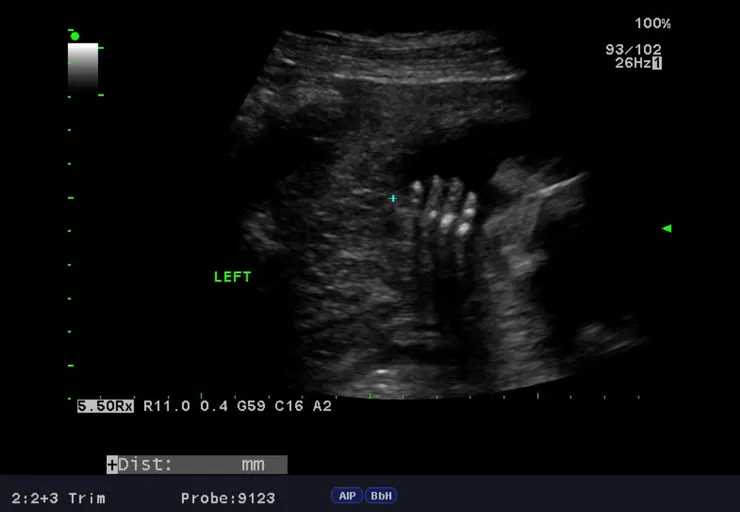

台兒的檢查並不是直接由醫師進行,是由放射師先針對外貌與所有器官進行第一輪初步的掃描,當時放射師照了照肚子裡的寶寶,正要進行著名的「數手指、數腳趾」程序時,寶寶很配合地張開了左手,讓我們數到了五根左手指,但右手卻一直緊握著,遲遲不肯張開,我喝了幾口特別準備的珍珠奶茶,放射師壓壓我的肚子,試圖讓寶寶活動起來,只見睡得香甜的寶寶,一點也不受外界干擾,放射師最後只好放棄,希望下一輪醫師掃描時,寶寶能熱情地張開雙手,完成手腳數數程序。